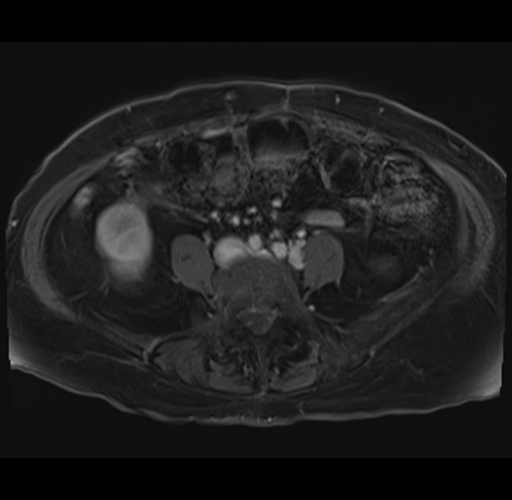

MRI T1